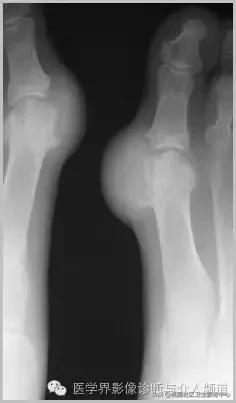

4、痛风石

为尿酸盐沉积形成,发生在关节周围软组织、包括韧带、肌腱、滑囊,眼、耳、鼻、喉、皮肤, 50%的钙化为X线平片可见。

痛风石,可见软组织肿胀及钙化灶。